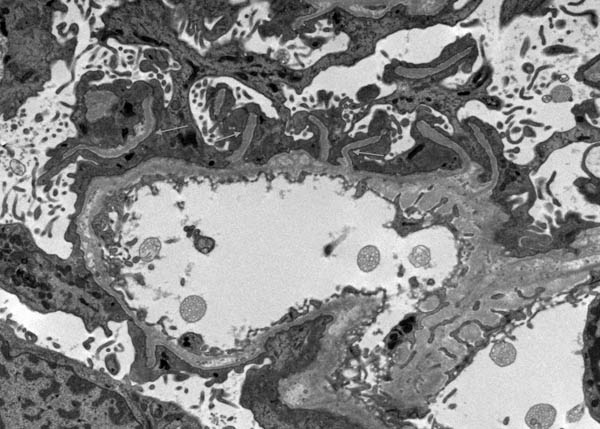

Electron microscopy showed unusual filiform projections of the glomerular basement membrane. These were fewer and longer than the spikes typically seen in membranous nephropathy (Fig. 2). There were also localised areas of glomerular basement membrane lamellation with electron-lucent areas and small electron dense granules (Fig. 3). There was extensive epithelial foot process effacement with microvillous transformation of podocytes. No electron-dense immune complex-type deposits were identified.